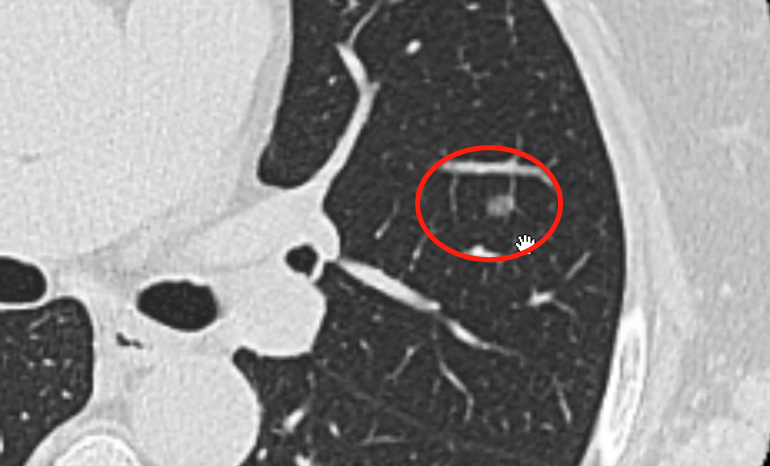

肺结节,恐怕是当今体检当中最让人纠结的一个小东西了。基本都是CT发现,尤其是一公分上下的,或明或暗,或半透明或实心儿,就像太空中一个外来星体,默默地呆在那里,让人始终揪着心。它到底是好是坏,会不会癌变,很难说清楚。 实在拿不准的,只能用时间来让它暴露。毕竟,人类还是更聪明。只要它沉不住气发生某些变化,就会被医生发现蛛丝马迹,斩于马下。 首都医科大学附属北京胸科医院胸外一科副主任医师杨志,跟我们分享了这样一个病例。这位女性患者自己也是医务工作者,53岁,六年前CT发现一个肺结节。刚发现的时候也确实拿不准,耐心地观察六年之后,一根小血管把这个结节的恶性本质暴露了。 这位患者是怎么发现的结节? 杨志:体检发现。因为她本身就是从事医疗行业,所以对自身的健康比较关注,每年都会做体检。六年前发现了左上肺叶的一块微结节的病灶。结节旁边有一支血管,这是一个可疑的血管滋养支,不是很明显,比较淡。 就说有一根小血管跟这个结节连在一起? 杨志:对,连在一起。大概0.8cm、0.9cm这个样子。 0.8cm、0.9cm,将近一公分了? 杨志:最长径不到一公分。 这其实在结节里头算是相对小的了? 杨志:对,应该叫微结节,算是最小的微结节,长径大概有0.9cm。 根据这个结节的形态,你们怎么判断它有没有问题呢? 杨志:首先在影像上,这块局部的微结节并不能判断是肺癌,但是我们根据增强CT扫描,又发现形成了供应营养的血管,癌的可能性就增加了。 就是说它连着跟血管的危险性就比较大了? 杨志:对,风险比较大。但是因为结节本身比较小,其实0.8cm、0.9cm这个体积的话,相对于肺内结节属于最早期的一个微结节,这种小于一公分的微结节,原则上是可以观察的。 那您建议她观察多长时间? 杨志:我建议她一年之后再复查。 那病人自己有没有表达担心,这结节一年以后会不会变? 杨志:也有担心。所以初期发现结节的话,如果病人也表示了比较明显的担心,那我们可以把检查周期缩短到半年,太近就不好了,就没有意义了,没有必要。另外病变的结节,是有一个变化的规律的,一般来说不会出现迅猛的增加。 那这位病人一年以后的情况呢? 杨志:一年之后其实也没有特别大的变化,还是那个样子,所以她一直在观察,保持间隔一年观察一次的频率。 她后来观察到什么时候? 杨志:观察到近期,近期是第6年的复查。第6年的复查图像我们发现异常了,病变比之前要变大了一些,而且颜色变深,密度增加。而且其中在血管进入的位置有一块稍白的部分,这说明有可能出现了浸润灶——浸润灶是癌细胞比较富集的位置,可能开始有往外的侵袭了。 就是癌细胞可能突破了原来“小球球”? 杨志:它也在这个“球”之内。在这个“球”之内,癌细胞开始往外渗透,我们在病理学上叫微浸润——微浸润就是对周围的组织开始出现侵袭性成长了。如果出现了微浸润的情况,就说明癌细胞有可能在近期内出现非常大的发展,往外扩增,就有可能出现转移。 就是从影像上“稍白”的部分可以看出它向外侵袭了? 杨志:对,这个地方比其他部分深一些,而且这只供养支血管比之前变粗了。供养支变粗了,肿瘤的内部又出现了实性灶,就说明癌的浸润性增强了。之前它可能是原位,它现在有可能变成在病理学上称作“微浸润性腺癌”的一种特殊的类型。影像上尽管不能确诊,但是我们长期经验还是高度怀疑的,必须警惕。 也就是这个结节有向外扩张的倾向,具备了恶性的特征? 杨志:对,基本上恶性的可能性非常大了。而且在出现微浸润性病灶的时候,它可能会出现一个比较迅猛的增长期,加上有血管的供养,这种增长期,有可能出现癌细胞脱落,顺着血管就流到全身其他器官了,有转移的风险,起码转移到淋巴结的风险要增加。而肺内淋巴结转移的情况,和生存期是非常相关的。 我们在临床上判断一个结节肺内结节,主要是一公分为限:小于一公分、一公分到两公分、两公分到三公分、超过三公分分成不同限度。在小于三公分的情况下,尤其1~2公分甚至小到1公分的情况下,5年生存率在微浸润腺癌的病理类型算,接近100%。 就是手术以后可以治愈了? 杨志:基本彻底治愈。而且我们所说的“5年生存率100%”是指无症状、无病患,是生活质量非常高的状态,因为相对来说体内无病。而且5年生存率高的话,后续的10年生存率、15年生存率都会非常高。 如果错过了这个时机,病变超过了一公分,或者达到两公分等等,它的5年生存率只能达到84%,降了很多,但是依然可以接受,84%也算相对较高的数字;如果再继续增加,达到2~3公分左右,这种情况只能达到60%多,65%左右,概率就非常低了。 60%多的生存率,是在用了各种治疗手段的情况下,化疗、放疗、靶向各种手段全用上,也不过是60%? 杨志:对,全部用上。另外在早期其实也不是特别建议使用这么强的手段,比如说化疗、免疫治疗,现在方法很多,但是一般来说不会用于早期患者,一般来说都是,出现问题之后,比如复发、转移,出现进展了,我们再用这些比较强力的“拳头”或者是方式。但是即使用了这种强力的方式,这种2~3公分的结节5年生存率还是不如人意,可能只有60%多。 假设出现了比较大的大块,5公分左右,甚至于更严重的情况,那么5年生存率非常迅速地降到50%以下,只有40%多。 这个不到一公分肺结节的患者,后来你们是怎么治疗的? 杨志:我们做微创手术把它切除了。做了个肺叶切除,淋巴结也清扫了,最终的病理报告提示微浸润性腺癌,跟我们术前影像判断的一样,而且淋巴结没有转移。这种情况对于她来说是非常好的,基本上就是5年生存率接近100%。 最后,杨志医生强调,这个患者6年前的结节就发现了细小的血管,并不能证明它就是恶性。良性肿瘤也可能有这样的现象。肺结节的处置,原则就是“不放过一个坏人,但也不能冤枉一个好人”,手术之前,尽量取得这个结节是恶性的证据,证据不明确,在确保安全的情况下,能不开刀就不开刀,尽量保全患者的健康肺。 肺结节手术,是个技术活儿,也是个良心活儿。